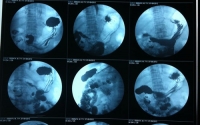

B超这个检查手段在医院里面是经常被用到的,而泽远医用B超胶片就是把检查结果呈现出来的一个方式,检查结果的造影会在B朝上面被显示出来,这样医生才好根据胶片上面的图片来判断来检查的人是不是患有某...